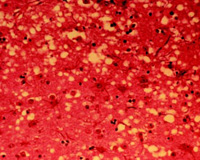

Photomicrograph of vacuoles—microscopic holes in the grey matter—gives the brain of BSE-affected cows a sponge-like appearance when tissue sections are examined in the lab.The name of the disease refers to the fact that as the disease progresses, the infected a…